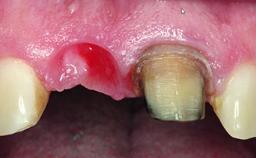

Replacement of an Upper Right Central Incisor with Root Resorption: Ridge Preservation, Delayed Placement of an NC Bone Level Roxolid Implant

A 32-year-old female Caucasian patient with a compromised maxillary right central incisor was referred to us by a general dentist. Her chief complaints were discomfort and mobility of tooth 11 with unsatisfactory esthetics due to discoloration. The patient reported a previous trauma, some years earlier, as the origin of pathology on the afflicted tooth. Anamnesis was negative for any other dental or periodontal pathology in the remaining dentition. The patient did not take any medication and reported to be a light smoker (5–10 cigs/day). She had high esthetic expectations of her treatment. The extraoral examination revealed a high smile line with full exposure of her maxillary teeth and surrounding soft tissue in the area between the second premolars.